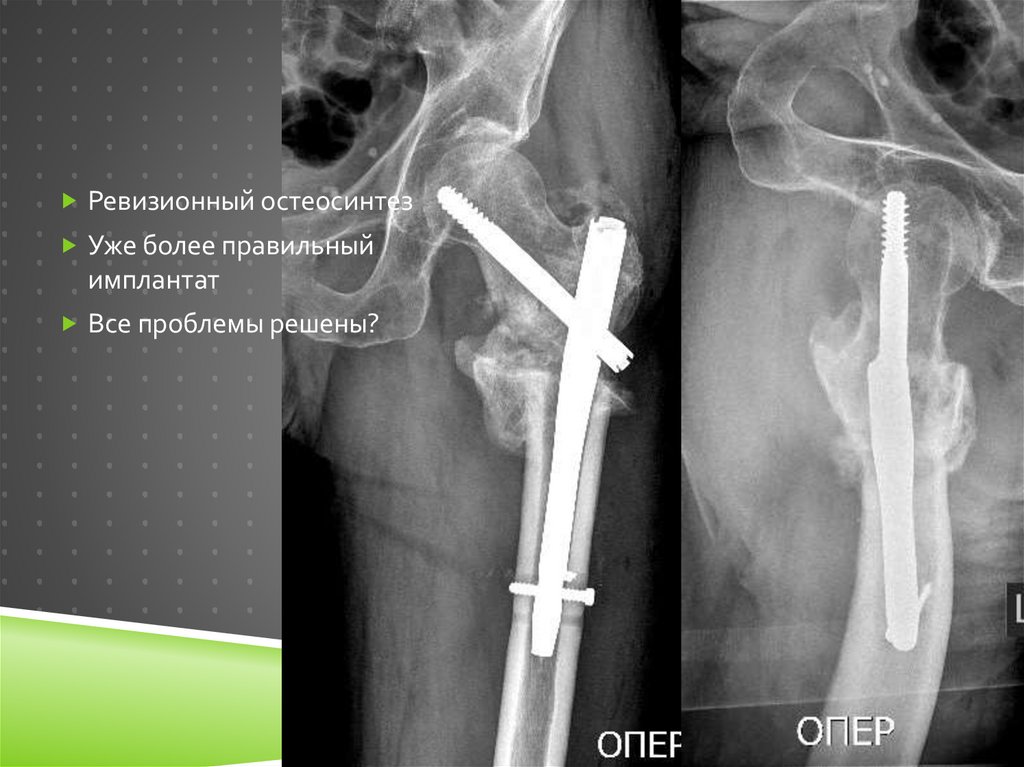

121.

Ревизионный остеосинтез

Уже более правильный

имплантат

Все проблемы решены?